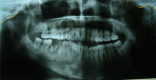

Facial asymmetry is one of the commonest facial anomalies, with reported incidence as high as 34%. Hemifacial microsomia (HFM) has an incidence of 1 in every 4000-5600 children and is one of the commonest causes of facial asymmetry. The standard treatment of HFM is orthognathic surgery by bilateral saggital split osteotomy (BSSO) or distraction osteogenesis (DO) of the mandible, both of which involve prolonged periods of occlusal adjustments by an orthodontist. Here, we present distraction of the mandible by means of a novel modified step osteotomy to correct the facial asymmetry in a case of hemifacial microsomia without disturbing the occlusion. This novel technique can prove to be a new tool in the maxillofacial surgeons armamentarium to treat facial asymmetry.